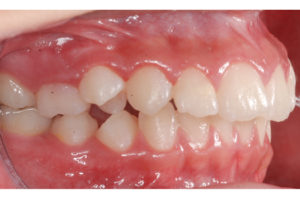

Documento utilizado en todo procedimiento odontológico y en cualquier especialidad, consiste en una secuencia de fotos faciales y dentales en diferentes ángulos, que permiten un diagnostico ideal y evaluar los avances del tratamiento al tener fotos posteriores, además es un documento legal.